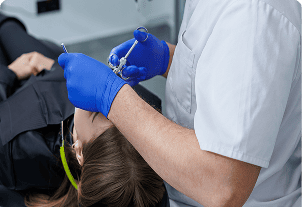

Anestezia lokale

Para fillimit të procedurës, aplikohet anestezi lokale për të garantuar rehati maksimale.

Riformësimi ose heqja e indit të tepërt të mishrave

Dentisti riformëson ose heq me kujdes indin e tepërt të mishrave duke përdorur mjete dentare moderne. Kjo ekspozon më shumë sipërfaqen natyrale të dhëmbëve, duke i bërë ata të duken më të gjatë dhe më simetrikë.